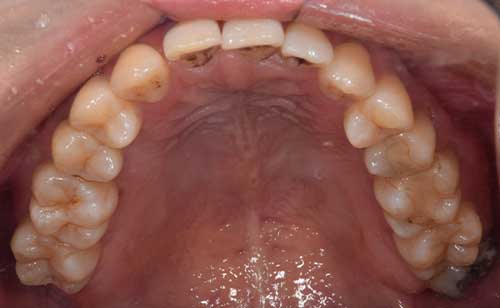

麻布十番歯科の親知らずの症例イメージ 麻布十番歯科の抜歯後の虫歯になっていた親知らずのイメージ